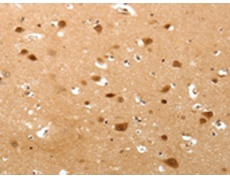

ELISA, IHC |

IHC positive control: |

Human brain and Human lung cancer |